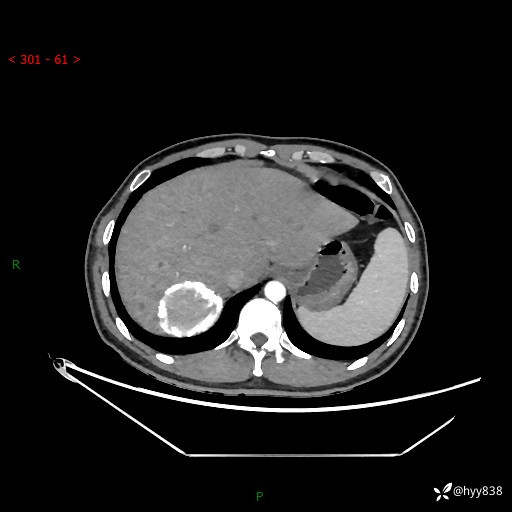

性别:男

年龄:50岁

简要病史:夜尿增多半月,发现肾功能异常1天,超声发现腹膜后占位

腹部CT平扫+增强

增强